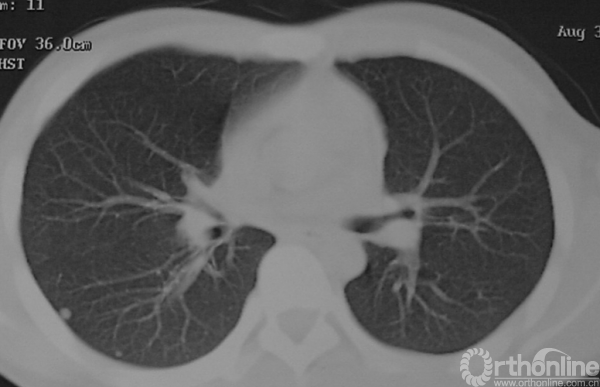

图14-9 入院时肺CT(第一次术后3个月),可见右肺结节影

1.应包含两部分内容,即局部范围和全身情况,因此需要做局部细致的影像学检查如CT、MRI,而全身检查则包括肺CT和全身骨扫描,甚至PET-CT。

2.即使已经出现肺转移,若局部不具备保肢条件,仍应行截肢手术,以降低局部复发风险。肺转移瘤的治疗应遵循外科手术与化疗相结合的原则。